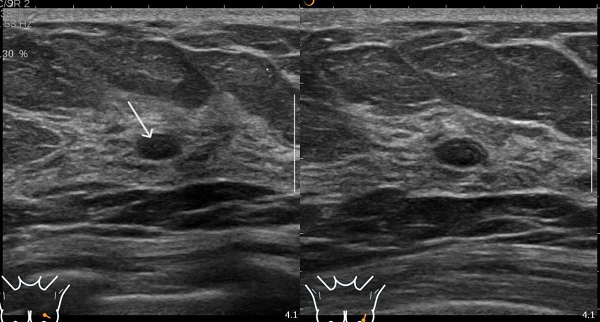

患者A钼靶显示“正常”,但超声发现囊肿和实性结节(如图1、2);

图2 患者A的超声表现图:(粗箭头处)乳腺囊肿,表现为无回声区;(细箭头处)乳腺实性结节,表现为低回声